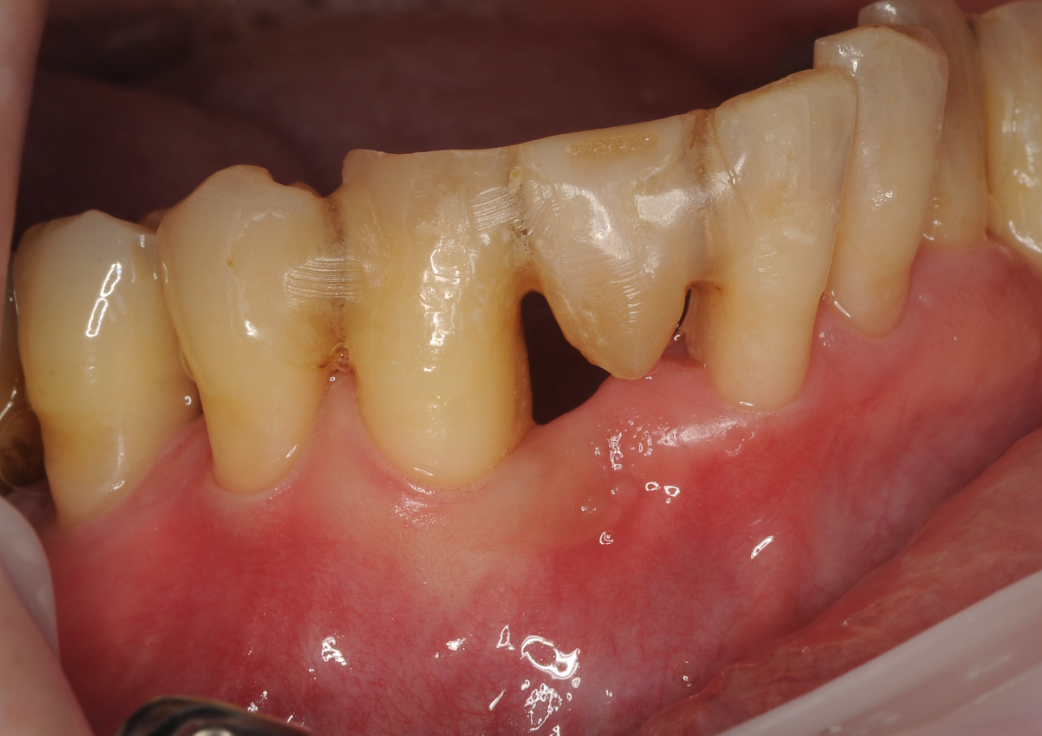

本日ご紹介する症例は去年の夏に初診で来院して頂いたダンディな方。

右下の犬歯の骨が完全に無くなっていました。

根尖まで骨がなく。。。。グラグラでした。

歯科ドックを行い、総合的な観点から判断し、歯周基本治療と

再生療法を行い

昨日の検査で数値が健康に戻りました!!